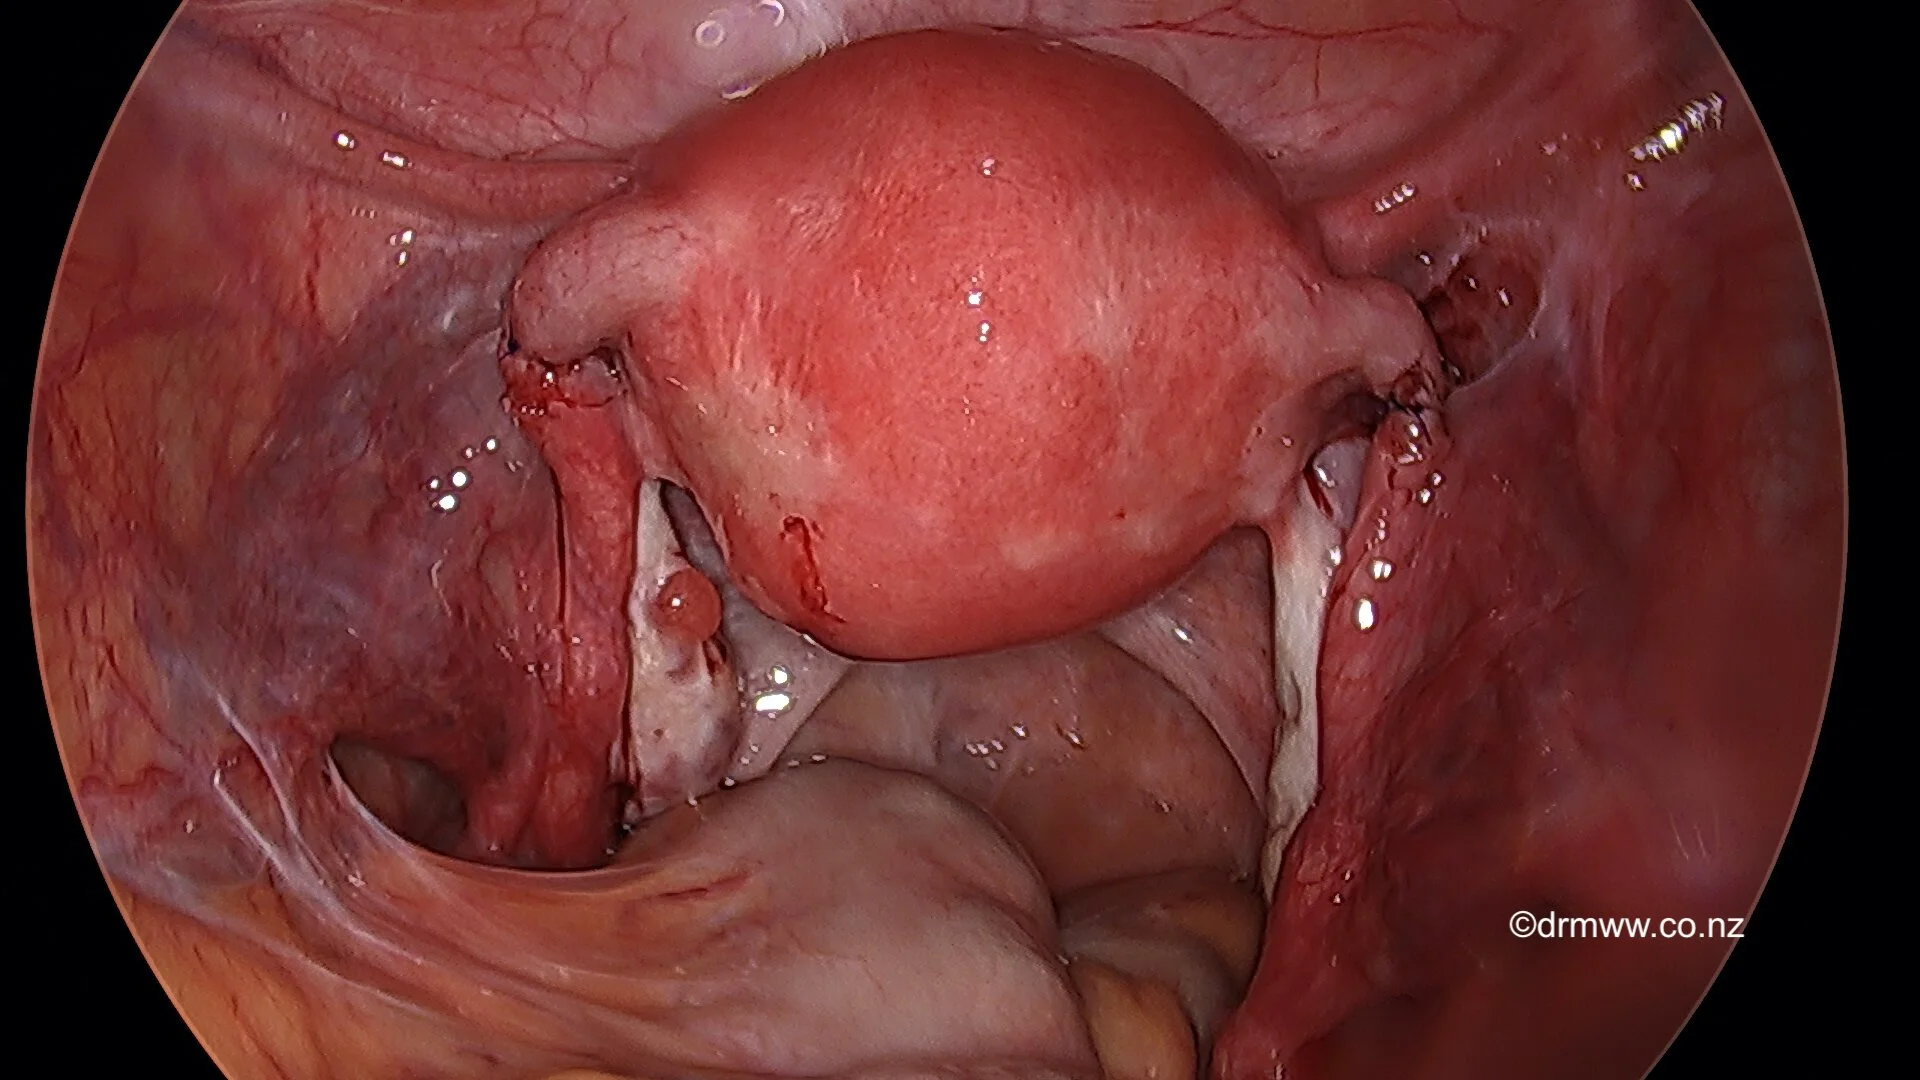

Laparoscopic view of previous tubal ligation (divided Fallopian Tubes)

The Fallopian Tubes are rejoined after the laparoscopic repair